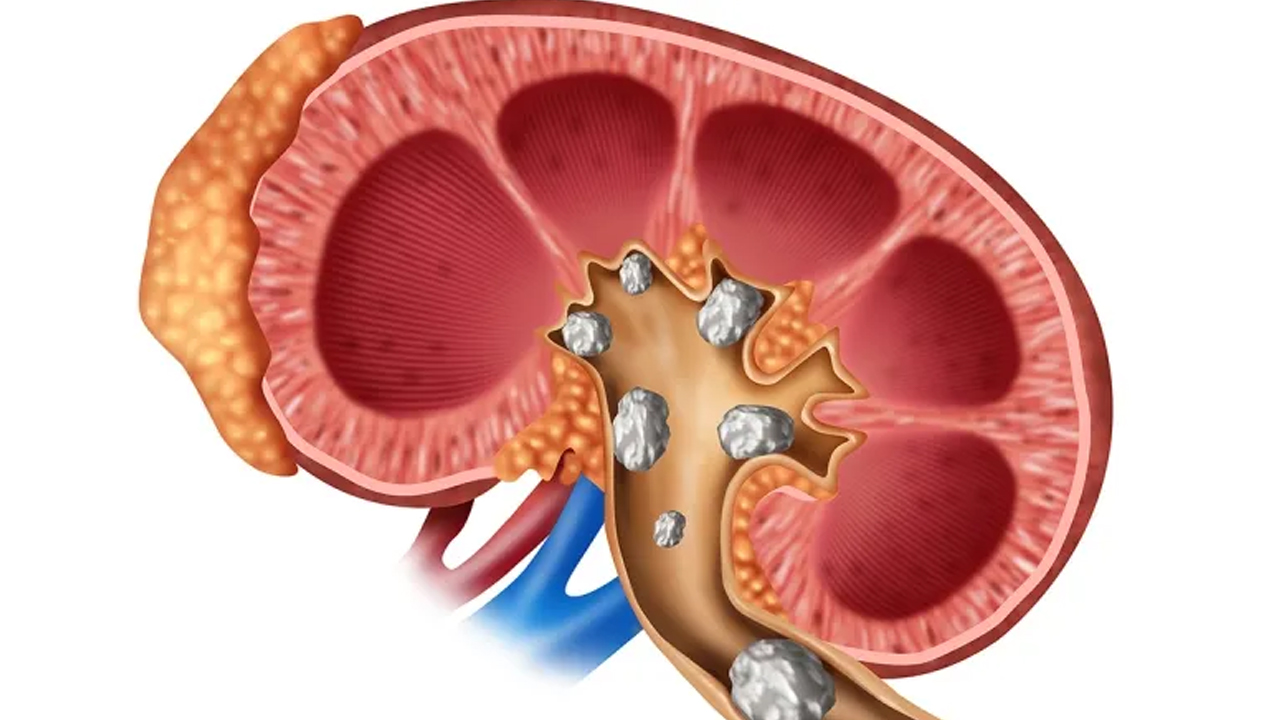

युरिक एसिड जुन प्यूरिनको विघटनबाट निस्कन्छ। तपाईंको रगत र मृगौलामा जान्छ। धेरैजसो अवस्थामा, यूरिक एसिड शरीरबाट पिसाबको माध्यमबाट बाहिर निस्कन्छ। कतिपय युरिक एसिड मल त्यागबाट बाहिर निस्कन्छ । यो समस्या तब हुन्छ जब शरीरमा युरिक एसिडको स्तर बढी हुन्छ किनभने यो पूर्णतया बाहिर निस्कन सक्दैन र तपाईंको जोर्नी र मृगौलामा स९साना पत्थरीको रूपमा जम्मा हुन थाल्छ, जसका कारण तपाईंलाई गाउट र पत्थरीको समस्या हुन सक्छ।

पिसाबमा युरिक एसिडको मात्रा बढ्नु पत्थरीको लक्षण होः नेशनल किड्नी फाउन्डेसनका अनुसार पिसाबमा युरिक एसिडको मात्रा बढी हुनु मिर्गौलामा पत्थरीको संकेत हुन सक्छ। जब युरिक एसिडको मात्रा बढी हुन्छ, यो मिर्गौलामा साना क्रिस्टलको रूपमा जम्मा हुन थाल्छ, जुन पछि ठूलो पत्थरी बन्न सक्छ।

मृगौला पत्थरका लक्षण:

तल्लो पीठ मा तेज दुखाइ, वाकवाकी, बान्ता, ज्वरो, चिसो हुनु ।